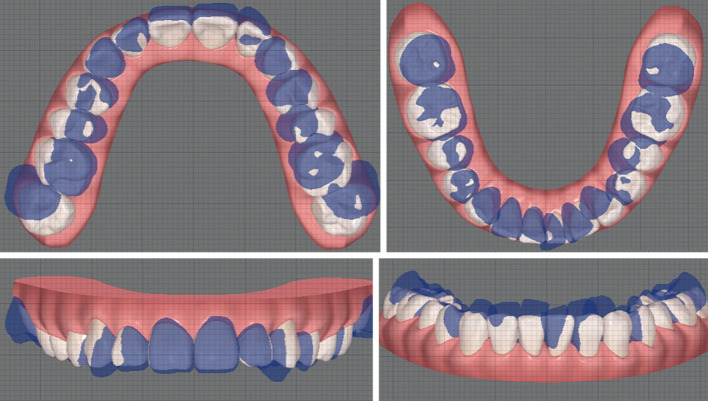

使用无托架的透明矫正器治疗双侧磨牙深覆咬合并颊交叉咬:一个病例描述。

Management of bilateral molar deep overbite with buccal crossbite using bracket-free clear aligners: a case description.